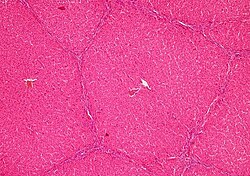

Qaraciyər mürəkkəb borulu vəzilərdən olub, bir çox paycıqlardan – lat. lobuli hepatis ibarətdir. Paycıqları təşkil edən atmalar qaraciyər epitel hüceyrələrindən əmələ gəlmişdir. Qaraciyər paycıqları şəkilcə çoxbucaqlı olub, bir-biri ilə birləşdirici toxuma vasitəsilə birləşmişdir. Paycıqların daxilində retikulyar liflərdən təşkil olunmuş tor vardır; bu liflər, ehtimal ki, qaraciyər kapillyarları endotelinin törəmələridir. Həmin endotel faqositoz vəzifəsinə malik ulduzabənzər (Kupfer adlanan) hüceyrələrdən ibarətdir.